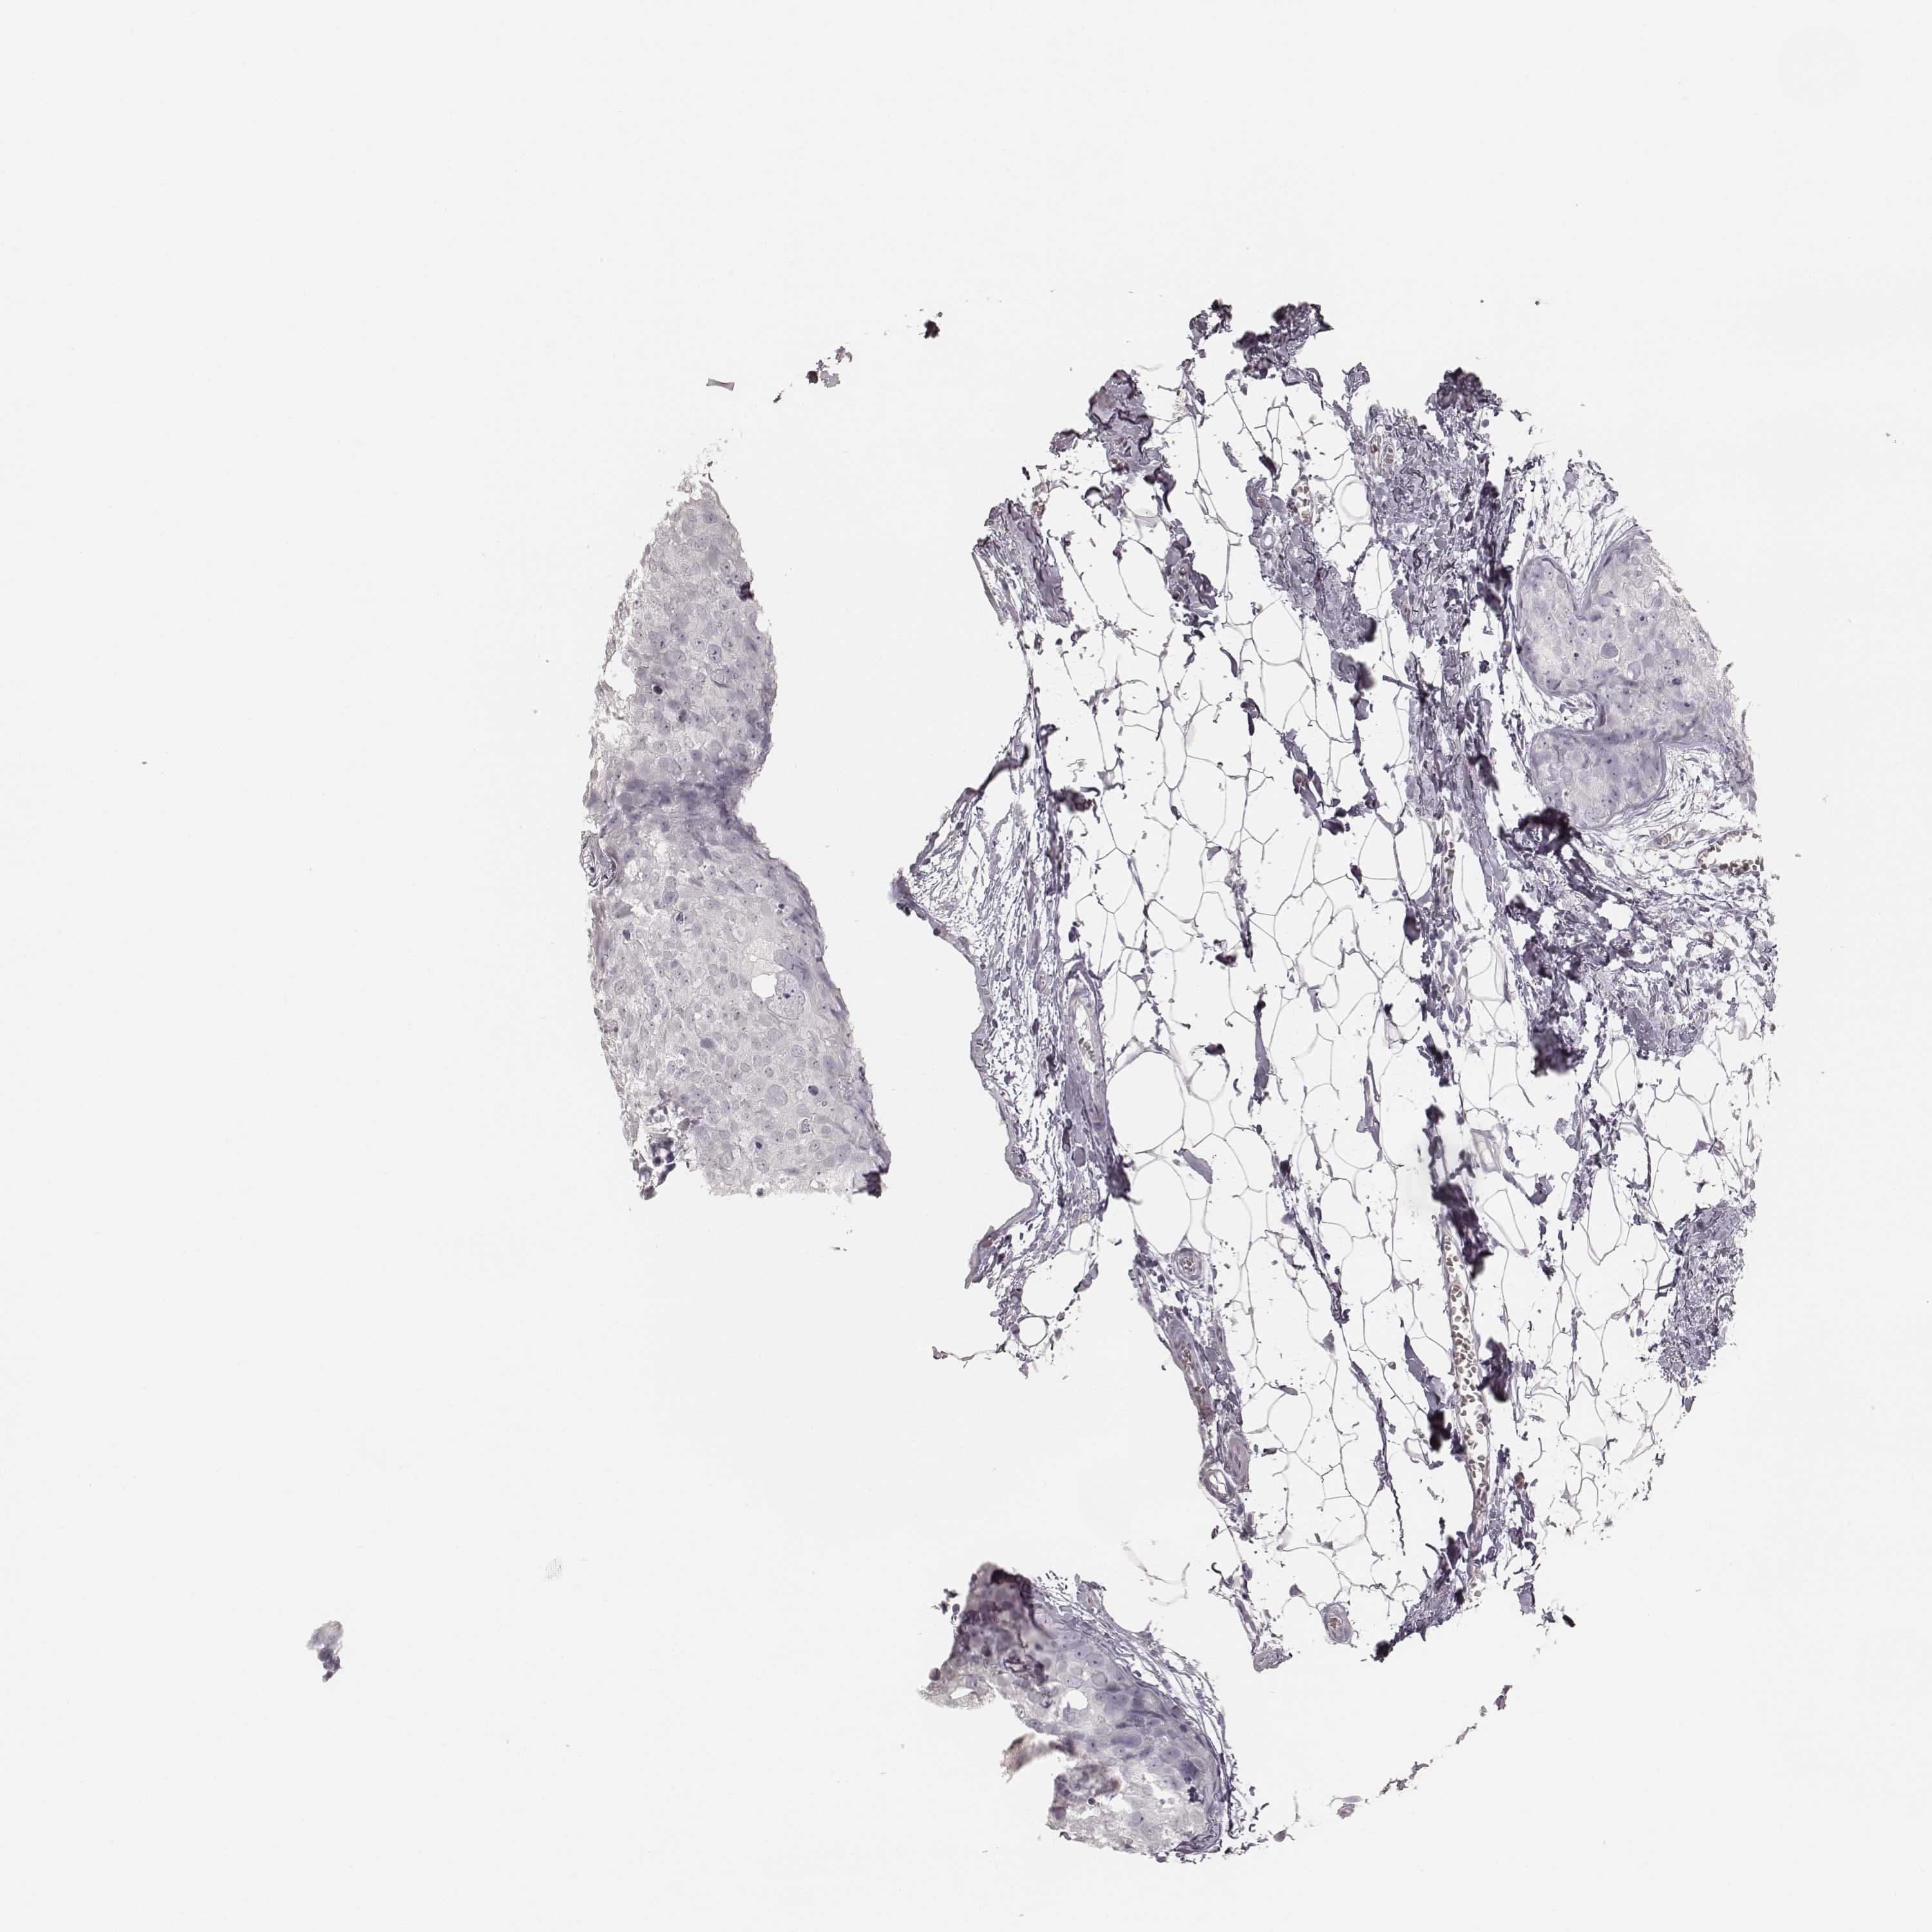

CANCER BREAST CANCER Show tissue menu

BRCA TCGA BRCA VALIDATION PROTEIN EXPRESSION

Breast cancer

Human cancer